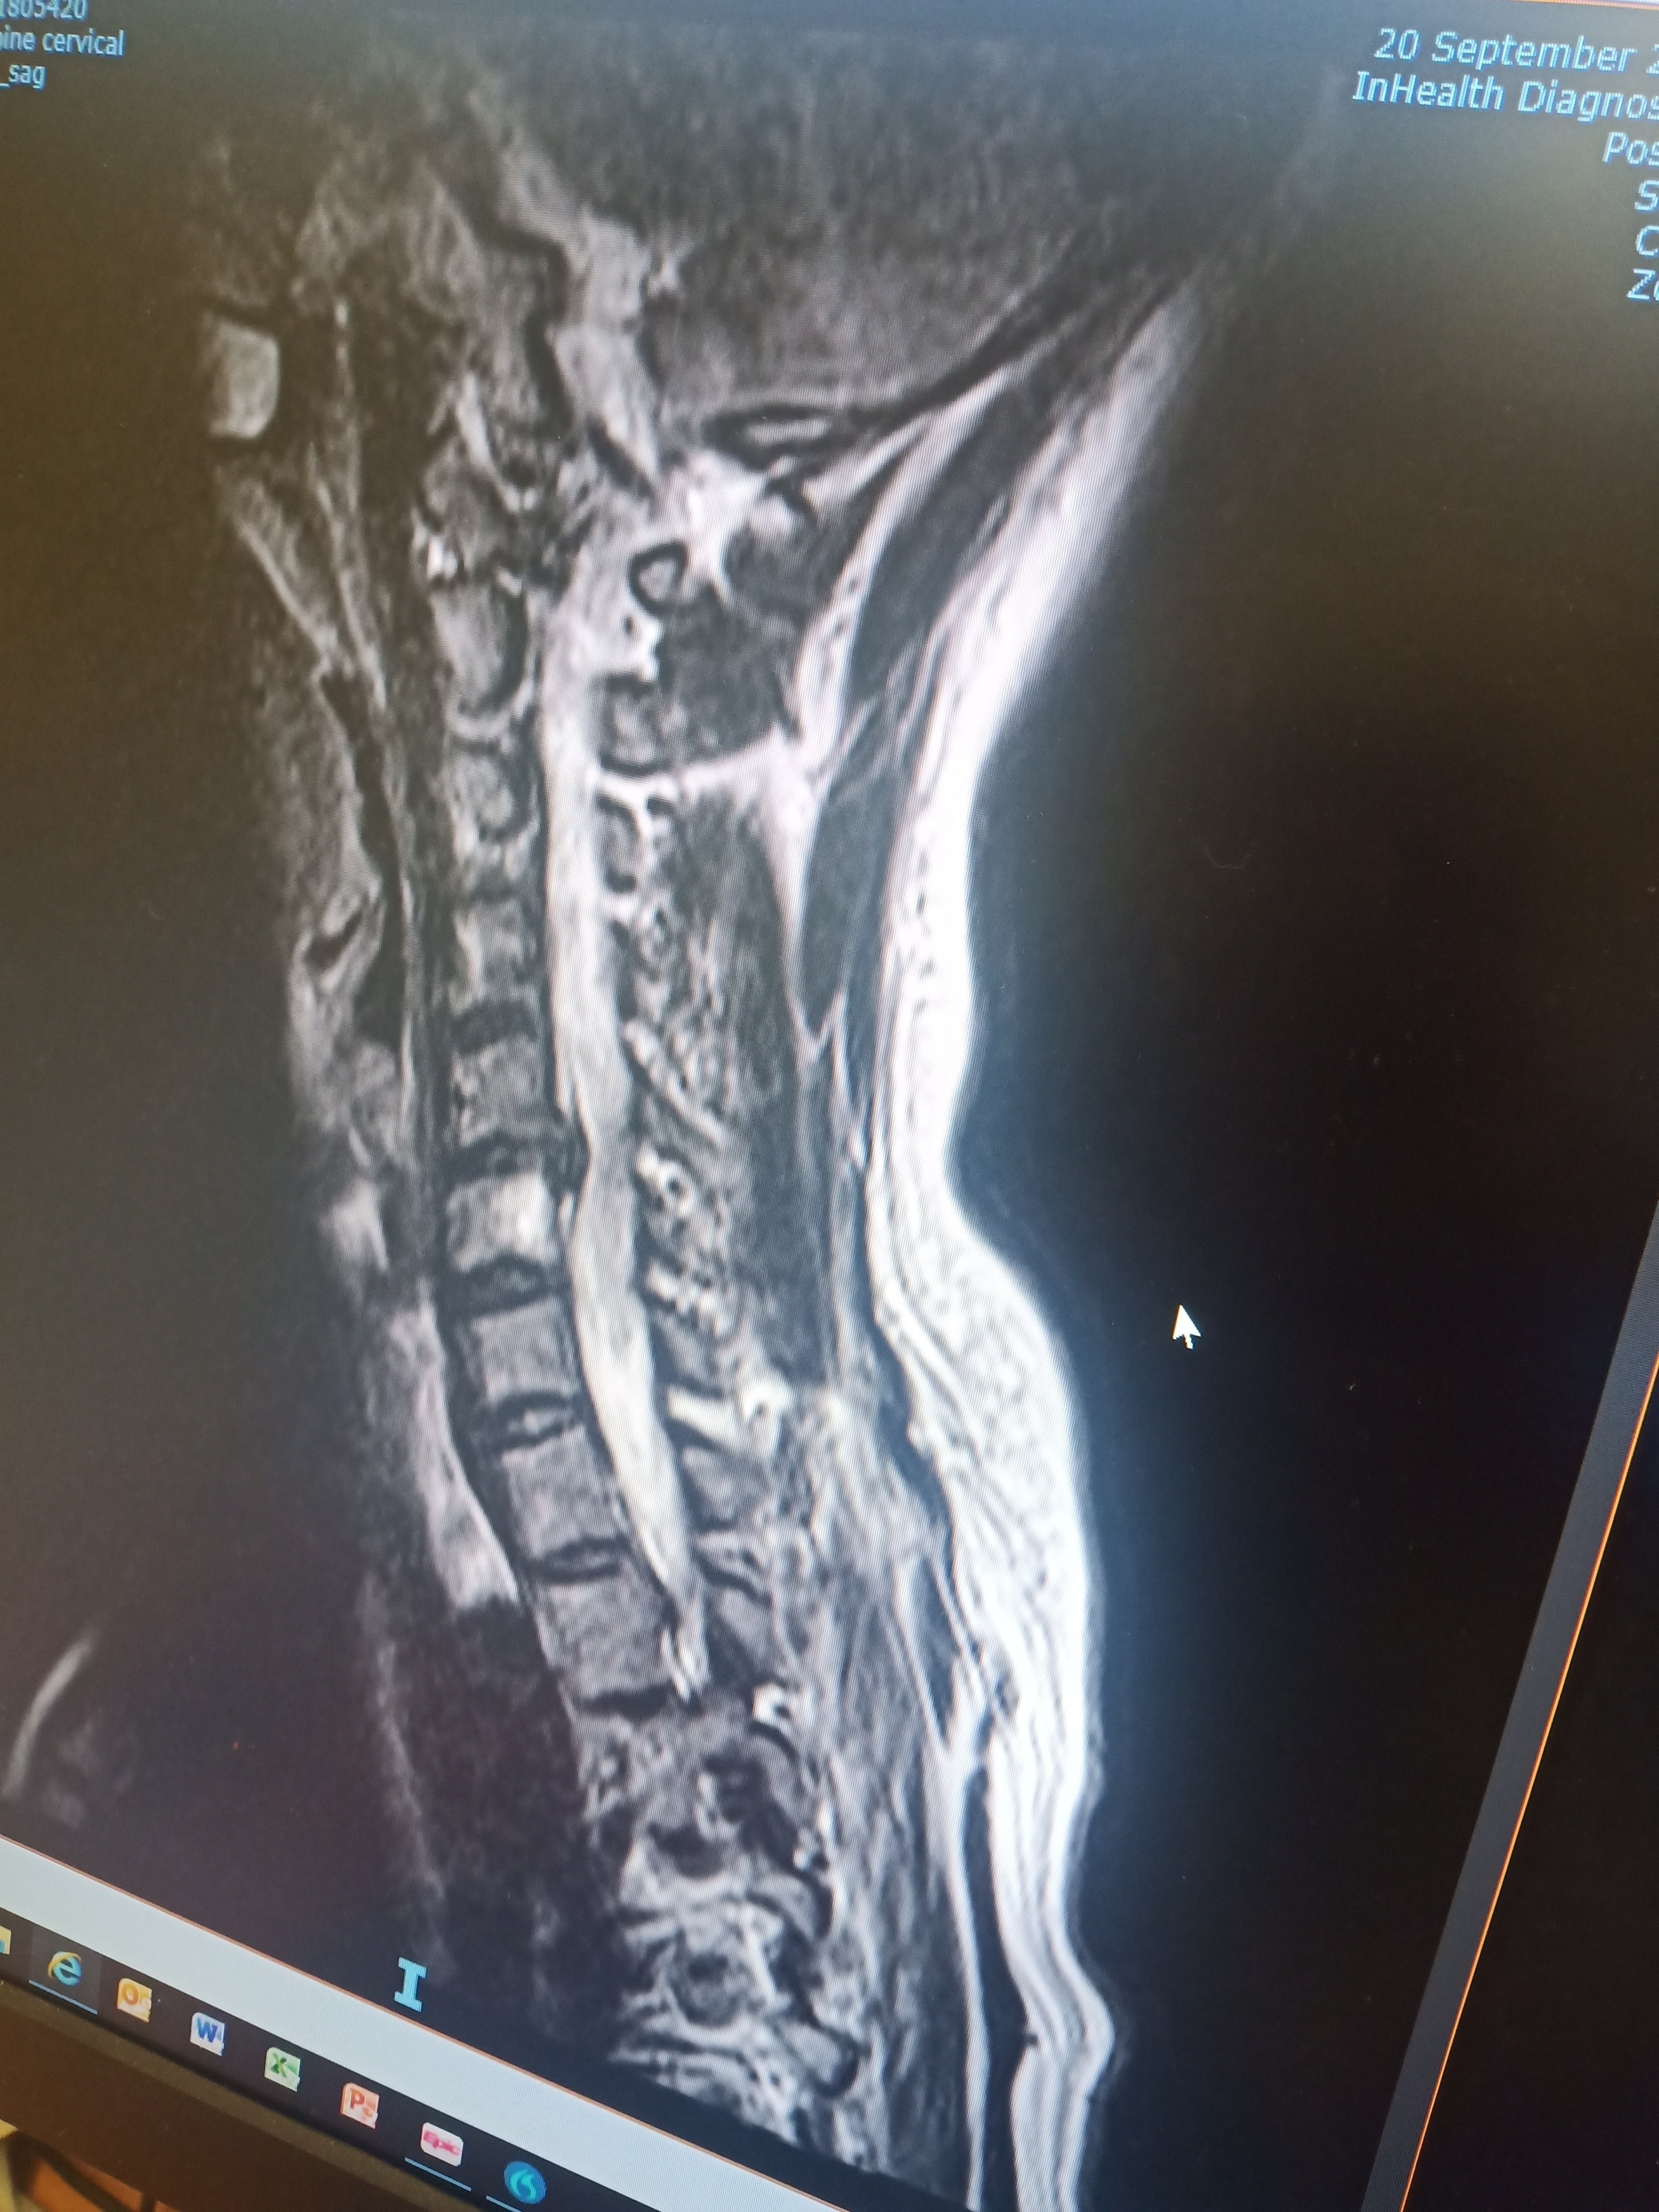

ストレートネック・椎間板ヘルニアと首の痛み(50代・女性)

長年、ストレートネックと椎間板ヘルニアによる首の痛みに悩み、さまざまな治療を試したものの、根本的な改善には至りませんでした。SBMを始めて数ヶ月で、首や腰の痛みが軽減。最初は身体の調整による違和感もありましたが、続けることで首の可動域が広がり、日常生活が快適になりました。2年後には首と腰の痛みがなくなり、首の後ろのコブも消失。さらに、出ていた椎間板が戻りました。正しいケアを続けることで、慢性的な痛みから解放されることを実感しました。